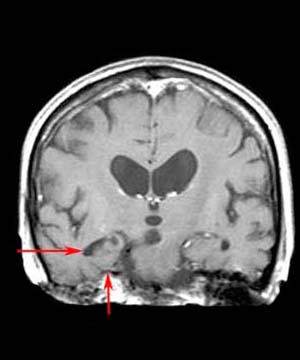

Because of its low sensitivity and specificity for the diagnosis of Alzheimer's disease, imaging is typically not used to rule in Alzheimer's disease but rather to rule out other causes of dementia. Nevertheless, in the right clinical context Alzheimer's disease appears radiographically as diffuse cerebral atrophy with enlarged lateral ventricles and widened sulci on CT. On thin-section (3 mm thick) coronal T1-weighted MR, medial temporal lobe atrophy primarily in the amygdala, hippocampus, and parahippocampal gyrus may be visually evident. Utilizing MR volumetric measurements, the hippocampal formation may be quantitatively determined to show focal atrophy. In addition, the temporal horns, supracellar cisterns, and Sylvian fissures may exhibit focal symmetric or asymmetric enlargement.

![]() ![]() MR has been chosen for the above images because of its ability to show greater detail in Alzheimer's disease. |